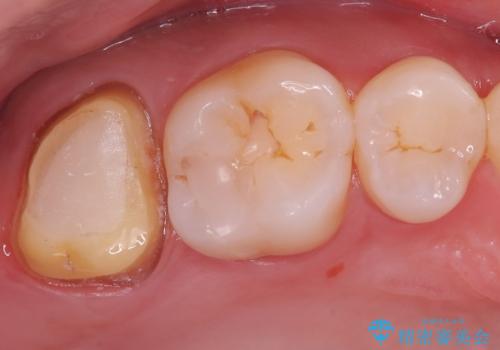

- 海外に転居する前に治療を完了させたいと来院された患者様です。

根管治療からセラミッククラウンまで来院回数は5回で治療を完了することができました。

治療前は遠心のポケットが7mmほどありましたが、治療後には3mmに改善しています。